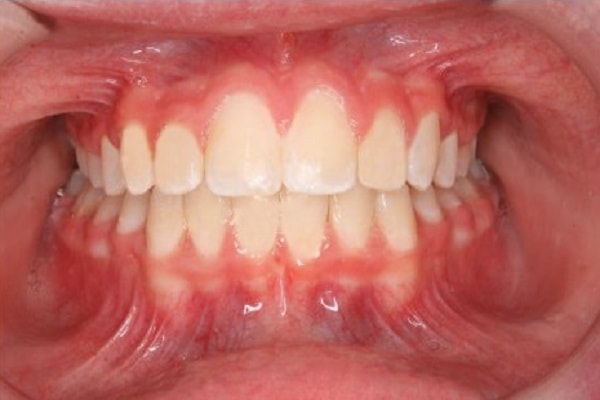

Treatment normally consists of braces that straighten misaligned teeth, crowded and protruding teeth, close gaps and align the bite so that the upper and lower teeth fit correctly when closing the mouth.

Aligning teeth can improve oral hygiene as your teeth will be easier to clean. Your bite will be better aligned to promote comfortable chewing.